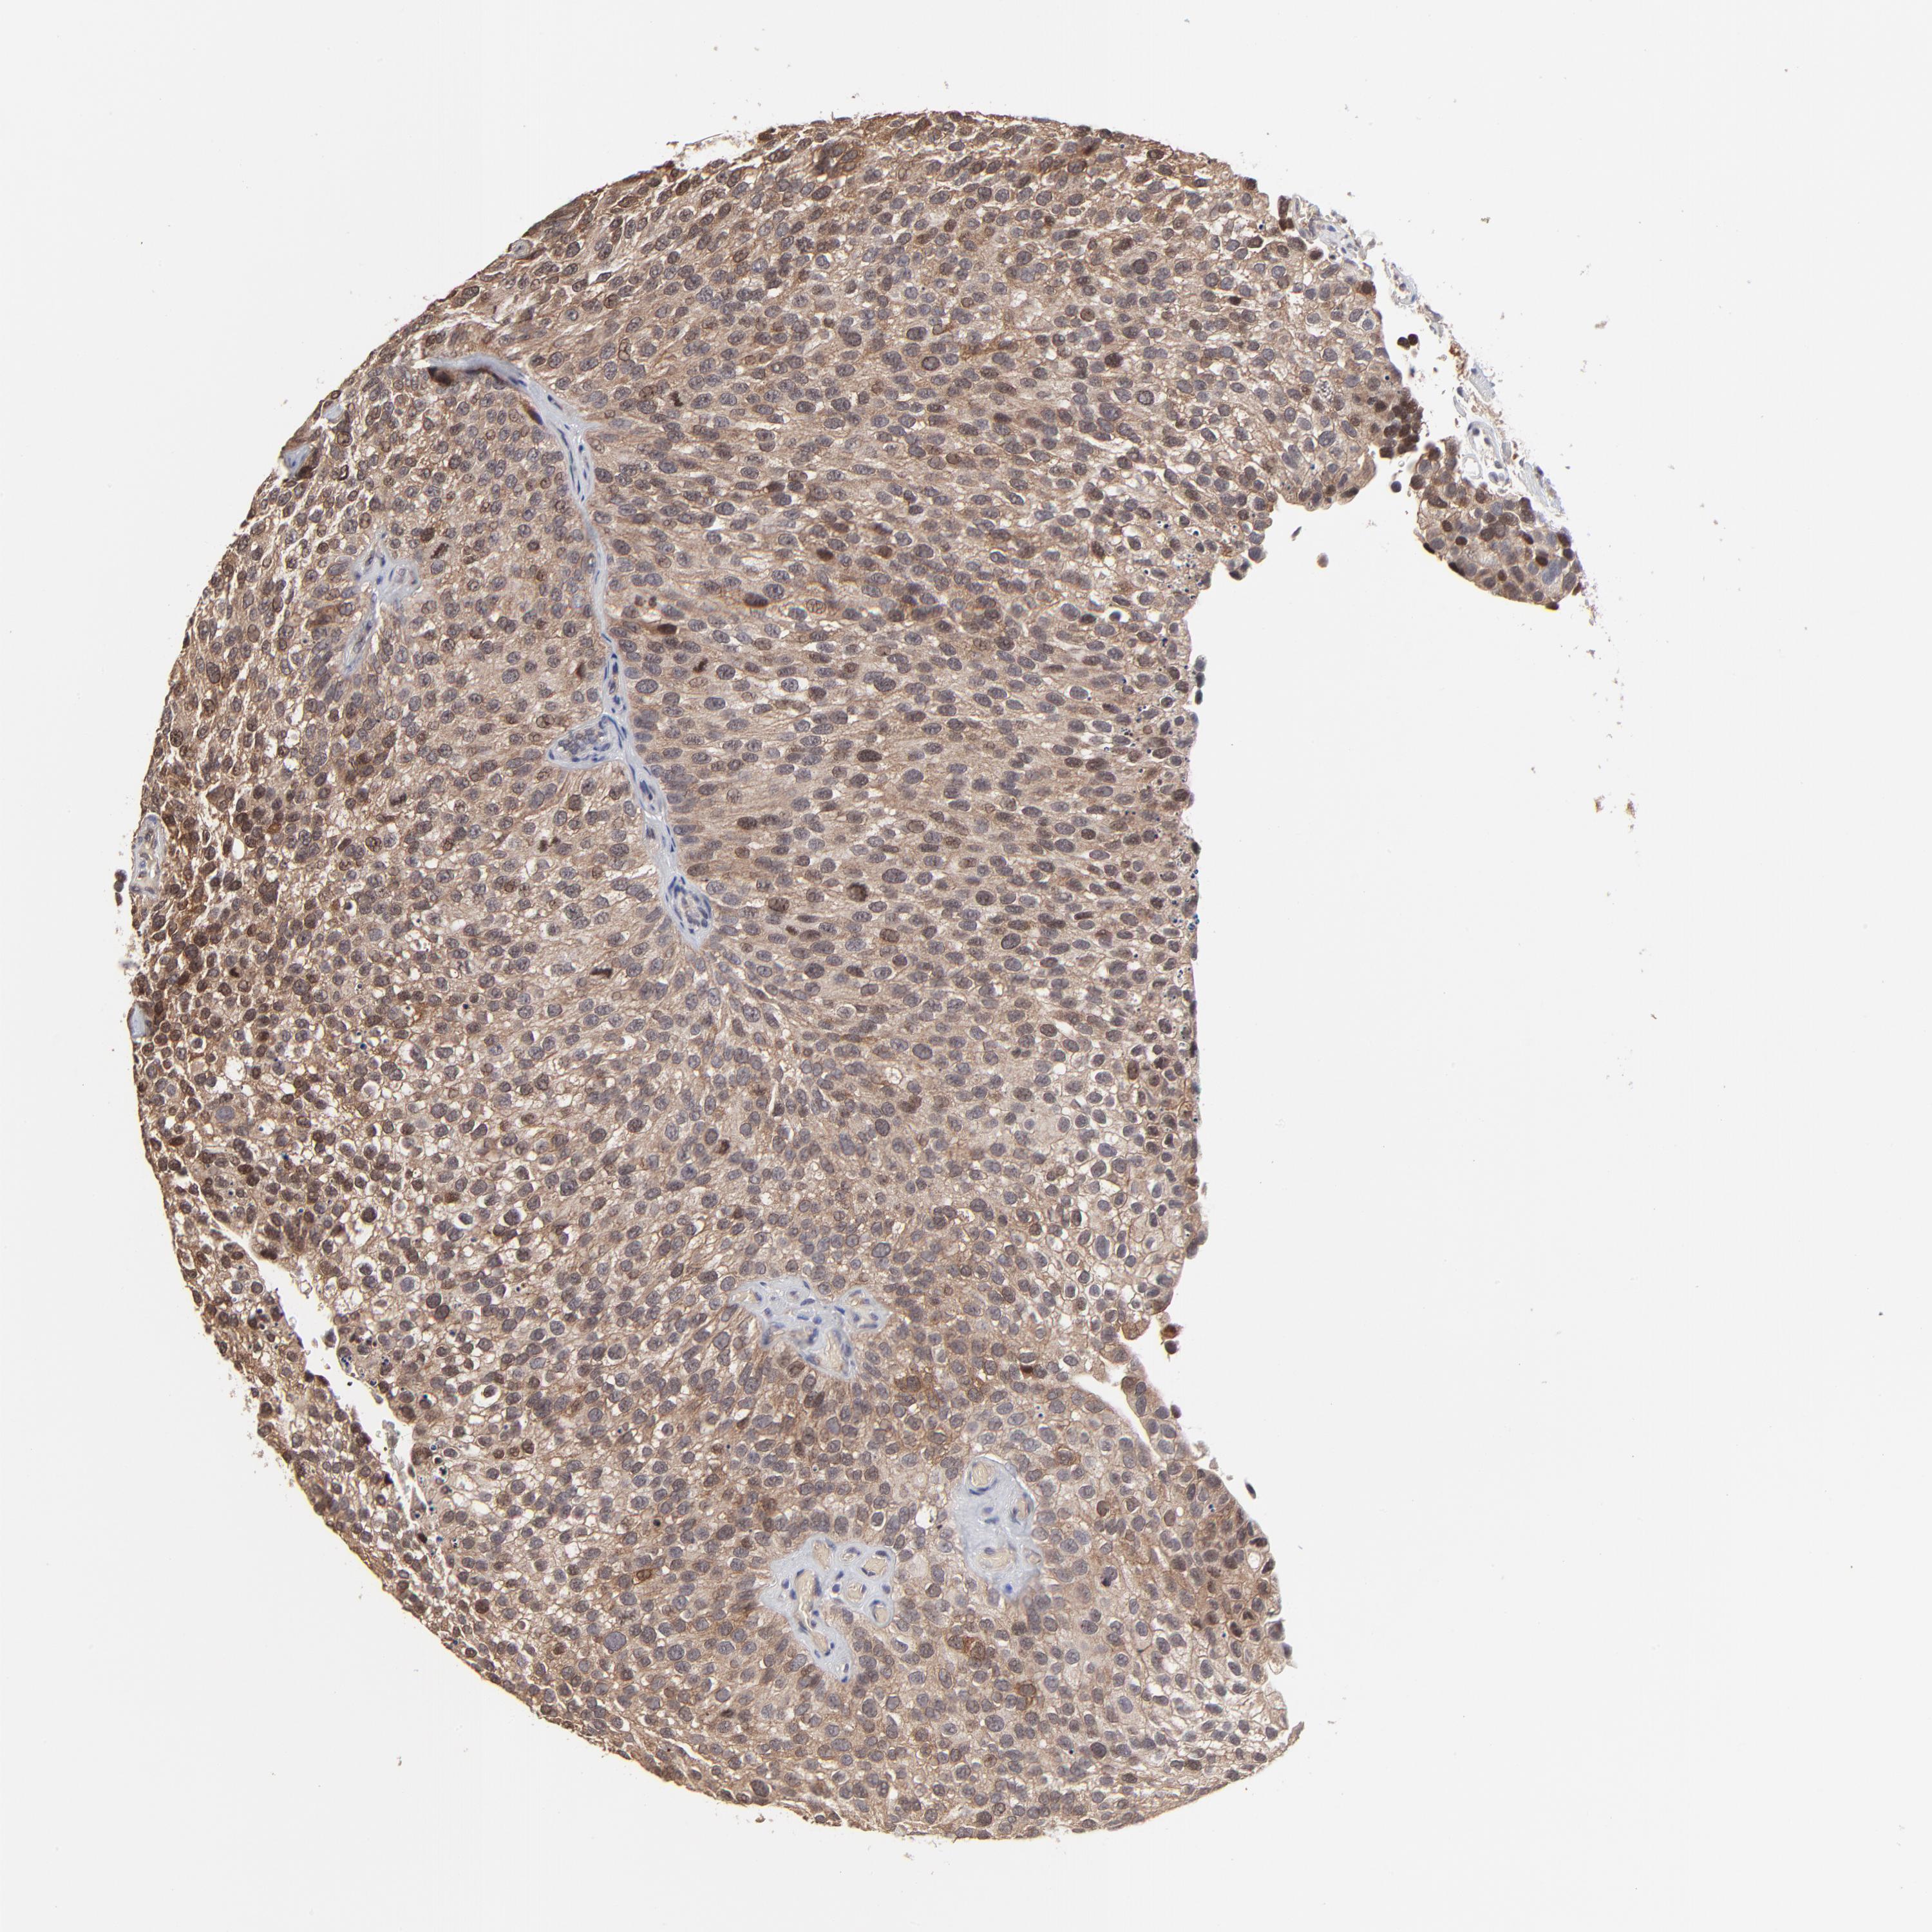

UROTHELIAL CANCER - Protein expressioni

A mouse-over function shows sample information and annotation data. Click on an image to view it in a full screen mode. Samples can be filtered based on level of antibody staining by selecting one or several of the following categories: high, medium, low and not detected. The assay and annotation is described here.

Note that samples used for immunohistochemistry by the Human Protein Atlas do not correspond to samples in the TCGA dataset.

Antibody stainingi

Antibody staining in the annotated cell types in the current human tissue is reported as not detected, low, medium, or high, based on conventional immunohistochemistry profiling in selected tissues. This score is based on the combination of the staining intensity and fraction of stained cells.

Each image is clickable and will lead to virtual microscopy that enables deeper exploration of all samples and also displays staining intensity scores, fraction scores and subcellular localization as well as patient and tissue information for each sample.

Antibody HPA002861

Staining

High

Medium

Low

Not detected

Intensity

Strong

Moderate

Weak

Negative

Quantity

>75%

75%-25%

<25%

None

Location

Nuclear

Cytoplasmic/membranous

Cytoplasmic/membranous,nuclear

Urothelial carcinoma, High grade

Urothelial carcinoma, Low grade